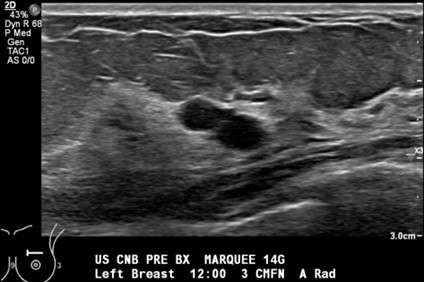

• Technologist confirms the lesion is still visualized and saves a pre-procedure image (Figure 1).

Procedure: US Guided Cyst Aspiration Figure 1

Figure 1. Grayscale sonogram shows two adjacent well-circumscribed, anechoic cysts at 12:00, 3 cm from the nipple.